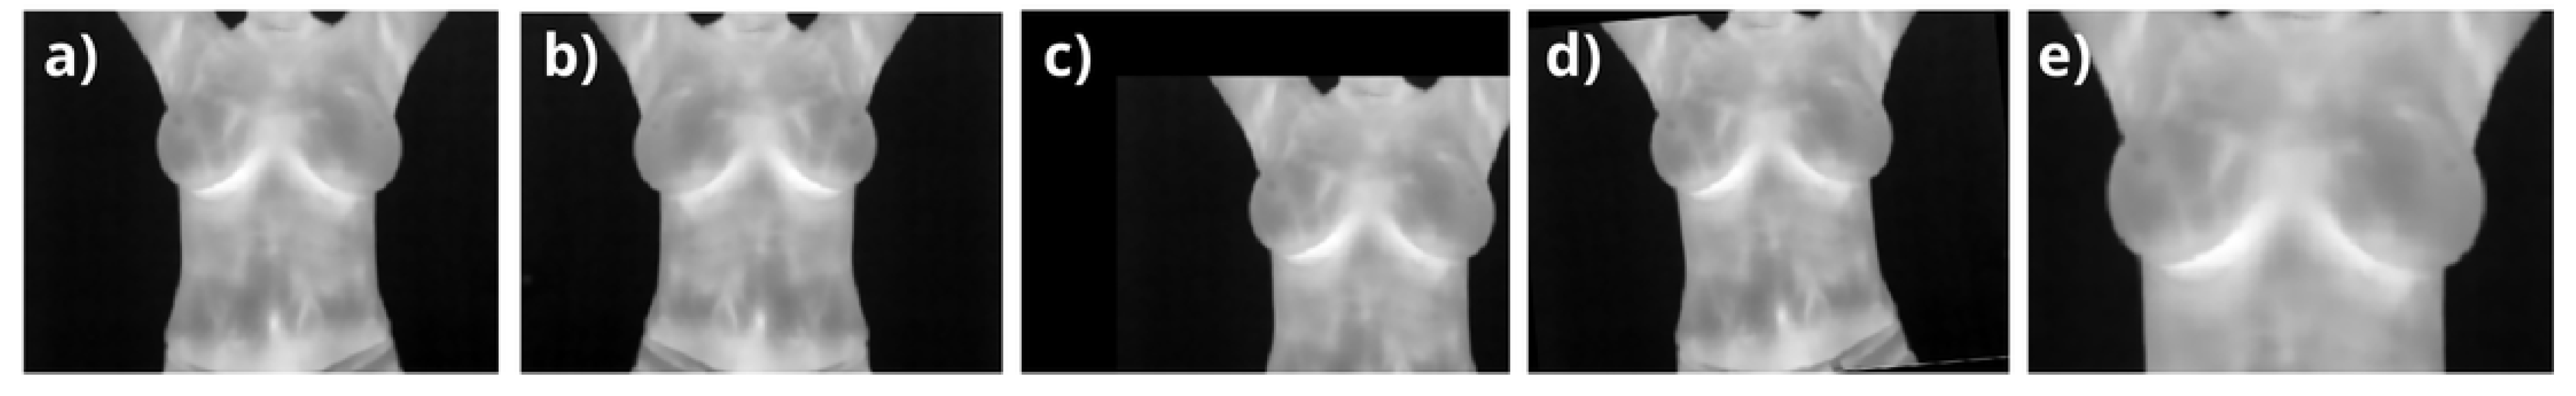

2.3.2. Data Augmentation

Data augmentation was applied as a prepropocessing stage during training and validation to enhance the diversity of the dataset while preserving anatomical realism, especially given the coronal nature of breast images. Transformations were applied to account for normal variations in human acquisitions, including width and height shifts ( ± 20 % ), horizontal flips, rotations within ± 20 , and zooming around the breast area (see Figure 4). These augmentations ensured that no abrupt or biologically implausible changes were introduced. Starting from the 126 training images, random variations were applied in each iteration, effectively simulating a larger dataset. Similarly, the 27 validation images were augmented to improve the robustness of hyperparameter tuning. The number of effective images processed by the network is proportional to the number of epochs ( 126 × n e p o c h s for training and 27 × n e p o c h s for validation), significantly improving generalization while preventing overfitting and maintaining clinical relevance. Starting with 126 base training images, augmentation expanded the dataset to simulate a total of 12,600 images over 100 epochs. Similarly, the validation dataset, initially comprising 27 images, generated 2,700 effective images over the same epochs. The dataset was processed in small batches of 8 images each, enabling efficient backpropagation during the training stages. This batch-wise approach allowed the optimizer, Adam, to iteratively adjust the model weights based on the gradient updates, ensuring a balance between computational efficiency and learning accuracy. By exposing the network to diverse augmented samples in each batch, the setup effectively minimized overfitting risks and enhanced generalization, ultimately optimizing the network’s capacity to learn meaningful patterns from the data.

Figure 4. (a) Reference coronal thermogram for data augmentation, showing breasts, armpits, neck, and abdomen; (b) horizontally flipped a); (c) vertical and horizontal shifts of 20%; (d) image rotated by 20 ; and (e) a zoom of 70% vertically and 80% horizontally in the upper breast region.